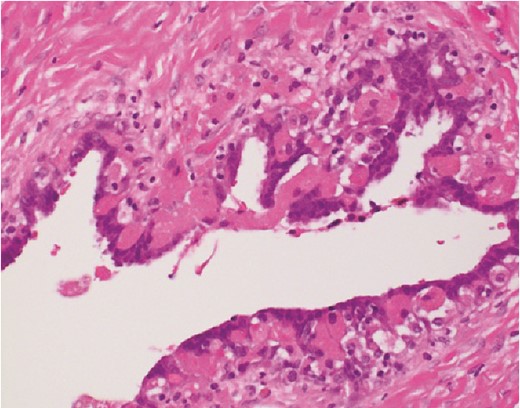

The histological findings with hematoxylin-eosin stain (H&E) revealed a cystic lesion with a very small and relatively dense stroma under the epithelium in the left paratubal region (Fig. 3). This stroma is CD10 positive in a small portion, suggesting the possibility of endometriosis (Fig. 4). Moreover, adenocarcinoma is arises from this cyst (Figs 5 and 6). There was no disseminated lesion in bilateral adnexa and uterus.